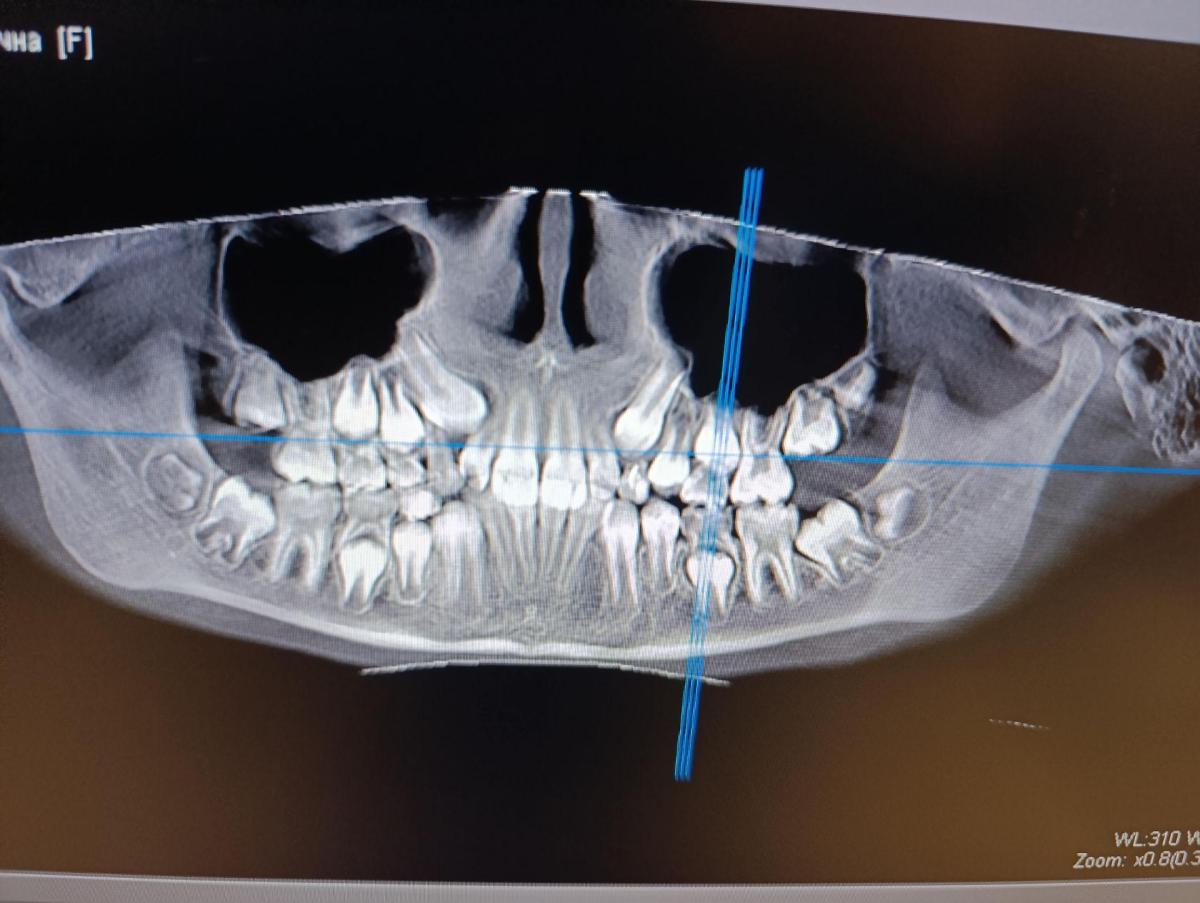

Nastya-Konovalova, для того, чтобы отвечать на вопросы, надо иметь обследование!